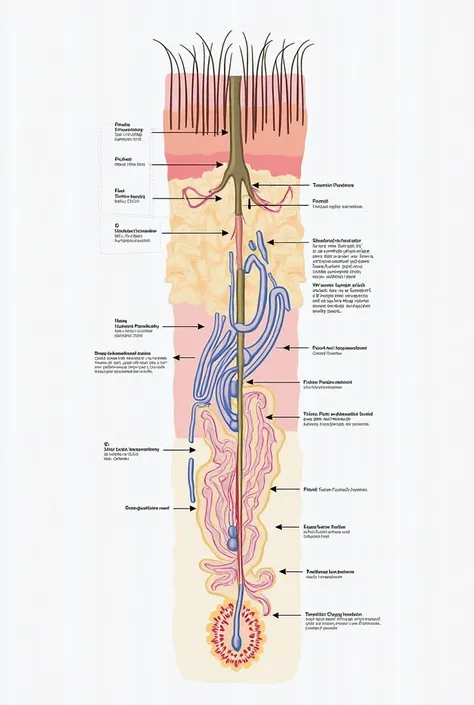

Realice un dibujo de la piel. Coloque las siguientes referencias: Epidermis Fermis Hypodermis Keratinized squamous stratified epithelium Hair Sebaceous gland Sweat gland Pilo erector muscle Connective tissue Blood vessels Nerves Adipocytes

Coloque las siguientes referencias:

Epidermis Fermis Hypodermis Keratinized squamous stratified epithelium Hair Sebaceous gland Sweat gland Pilo erector muscle Connective tissue Blood vessels Nerves Adipocytes